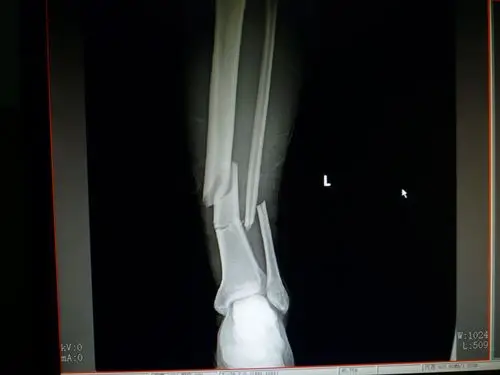

胫腓骨远端骨折

王永刚,男,44岁,胫骨远端骨折,18年8月24日入院,9月1日手术

三例胫腓骨远端骨折

胫骨远端骨折的诊断,治疗 [病例帖]